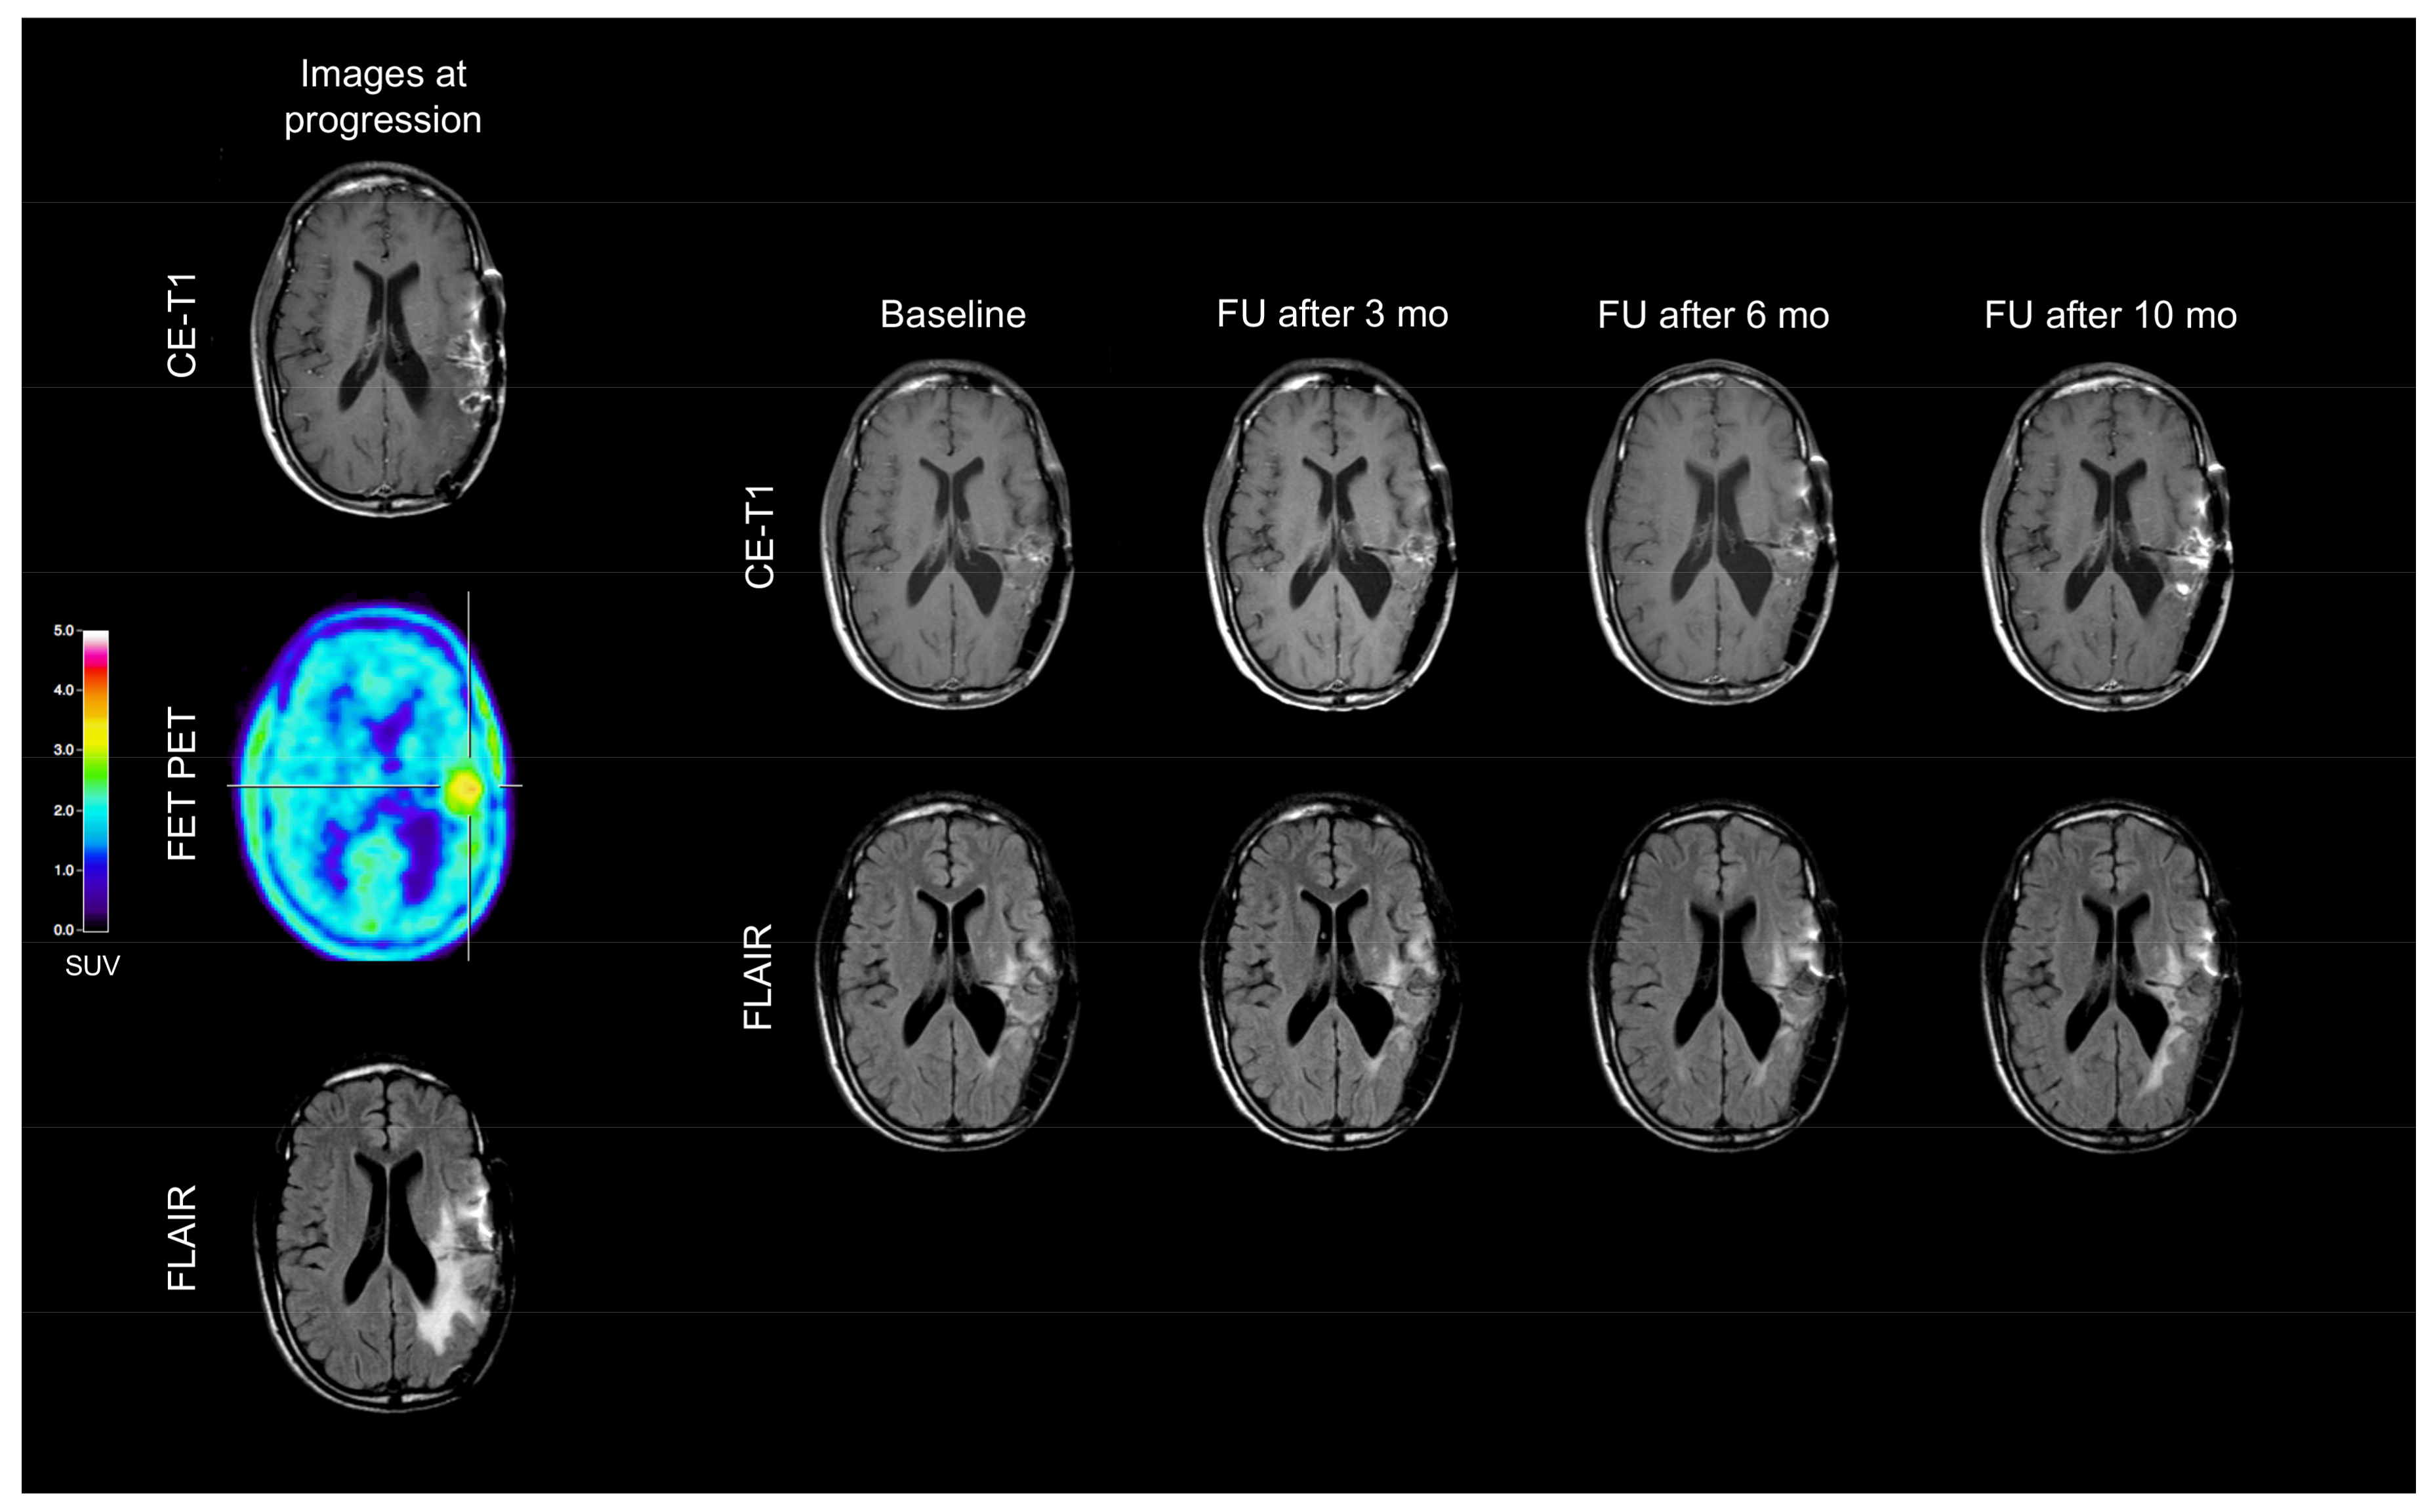

2. Case Description